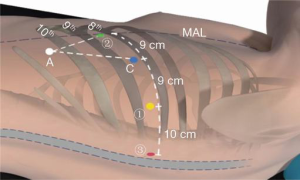

The position for the robotic ports is marked on the skin along the eighth intercostal space, as noted in Figure 2. Robotic arm No.3 is located 3 cm from the spine (most posterior), robotic arm No.1 (right arm) is 9 cm from robotic arm No.3, the camera port is 9 cm from robotic arm No.1, and robotic arm No.2 is 9 cm from robotic arm No.1 (most anterior). An assistant port is triangulated behind robotic arm No.2 (the left arm) and the camera port, as low in the chest as possible without disrupting the diaphragm. The camera port is placed initially, which permits carbon dioxide insufflation of the left chest to 15 mmHg. Once all ports are placed, the robot is docked. A cadiere instrument is used for the left robotic arm and a curved bipolar dissector is used for the right robotic arm. A thoracic grasper is used for robotic arm #3, and can assist with retraction of the lung or the mass.